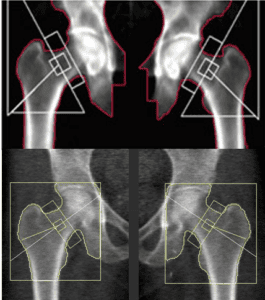

Comparison of image quality between clinical and retail scans

Accuracy in measurement is also critical. For hip scans, it is essential that the neck of the femur is measured at the narrowest part [4]. Retail scans often fail to accurately identify and measure this specific area.